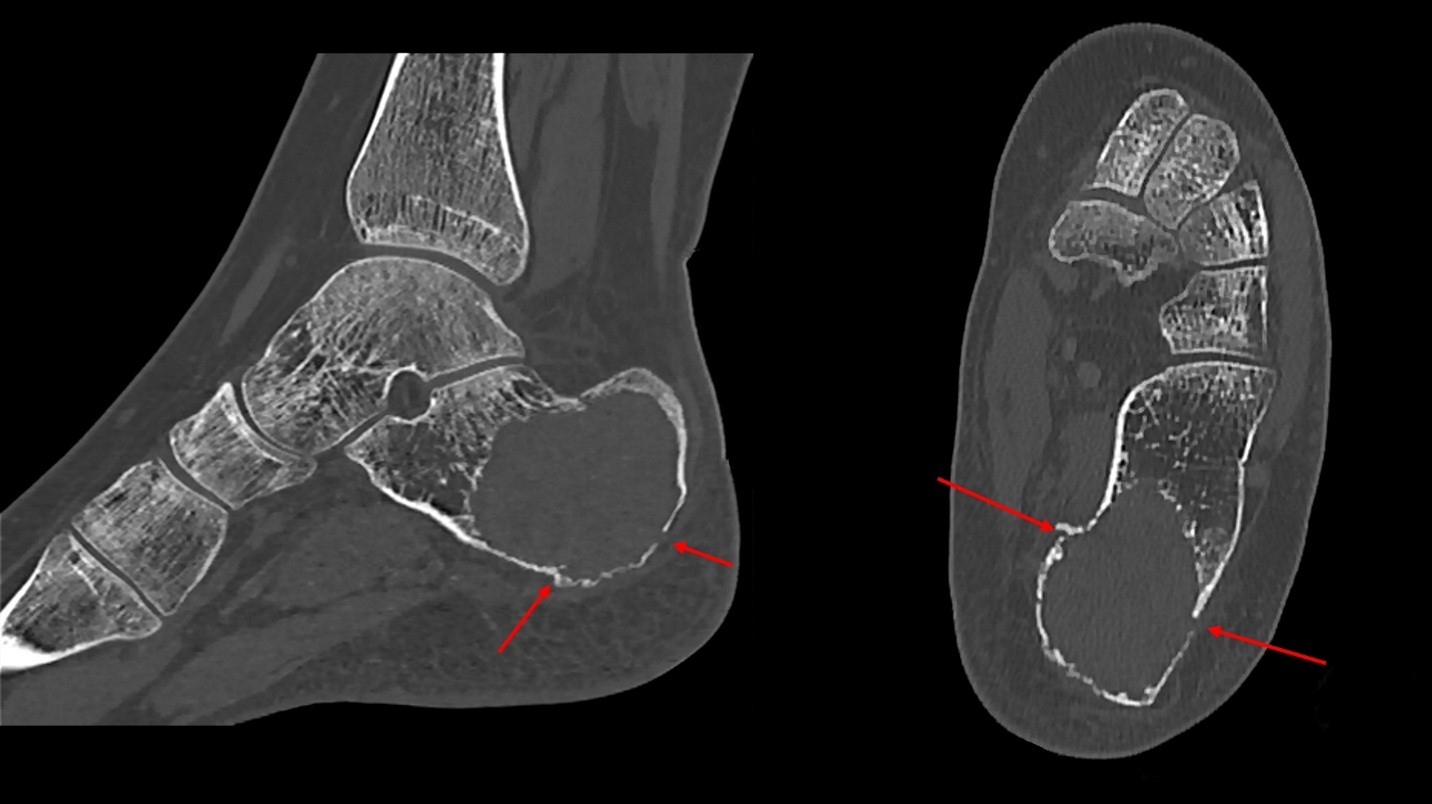

Leading differential on the radiology report included aneurysmal bone cyst. Magnetic Resonance Imaging (MRI) of the hindfoot was recommended by radiology for further evaluation. Prior to obtaining an MRI, the patient tripped, injuring her left foot. Computed Tomography (CT) was performed showing a pathologic extra-articular fracture through a lytic lesion in the posterior calcaneus with mild displacement (Fig. 2).

Figure 2: CT of the left ankle showing lytic lesion in the posterior calcaneus with multiple extra-articular fractures lines (red arrows) extending through the lesion with mild displacement. Consistent with pathologic fracture. On the left is lateral view and on the right is axial.